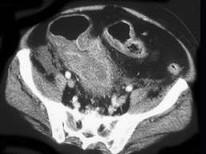

问题 男,18岁,患者皮肤挫伤,用林可霉素预防感染,次日大便次数增多、出现粘液便,结合图像应考虑为 ( )

选项 A.结肠淋巴瘤 B.假膜性肠炎 C.结肠间质瘤 D.结肠结核 E.结肠癌

答案 B